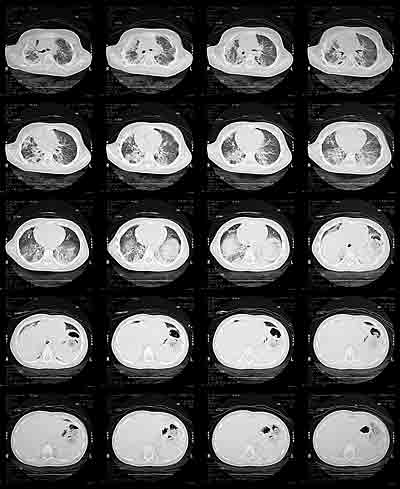

A high resolution CT of the chest was ordered next to help delineate the pattern of her lung disease better.

HRCT chest from May 29th

CT of the chest showed essentially the same findings as the CXR and confirmed

the interstitial pattern. You can see that the disease is very generalized

but now worse on the right side than on the left, with mediastinal shift

to the right.